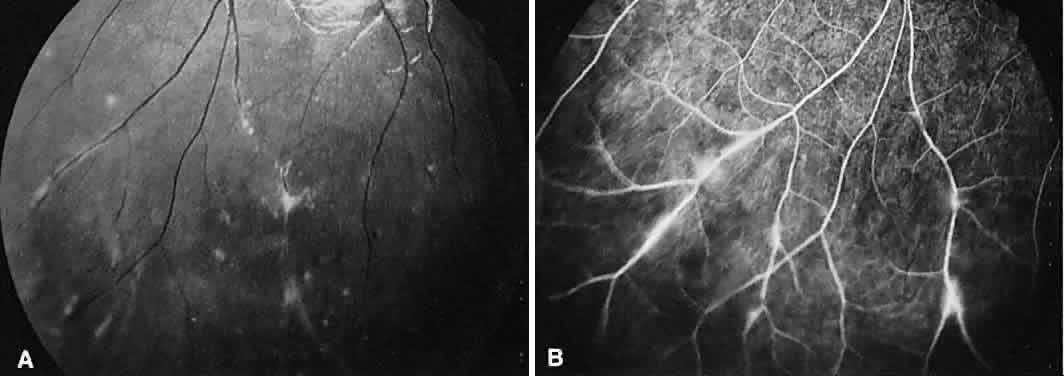

Fig. 9. Intermediate uveitis. A. Red-free photography of the peripheral retina shows sheathing of the retinal venules. B. Fluorescein angiography shows staining of the vessel walls with leakage from the peripheral venules.

On fluorescein angiography, there is venular wall staining (Fig. 9),30 hyperfluorescence, and leakage of the peripheral inflammatory membranes.31 Cystoid macular edema often is evident.30 Optic disc, peripheral retinal, and subretinal32–34 neovascularization are rare.